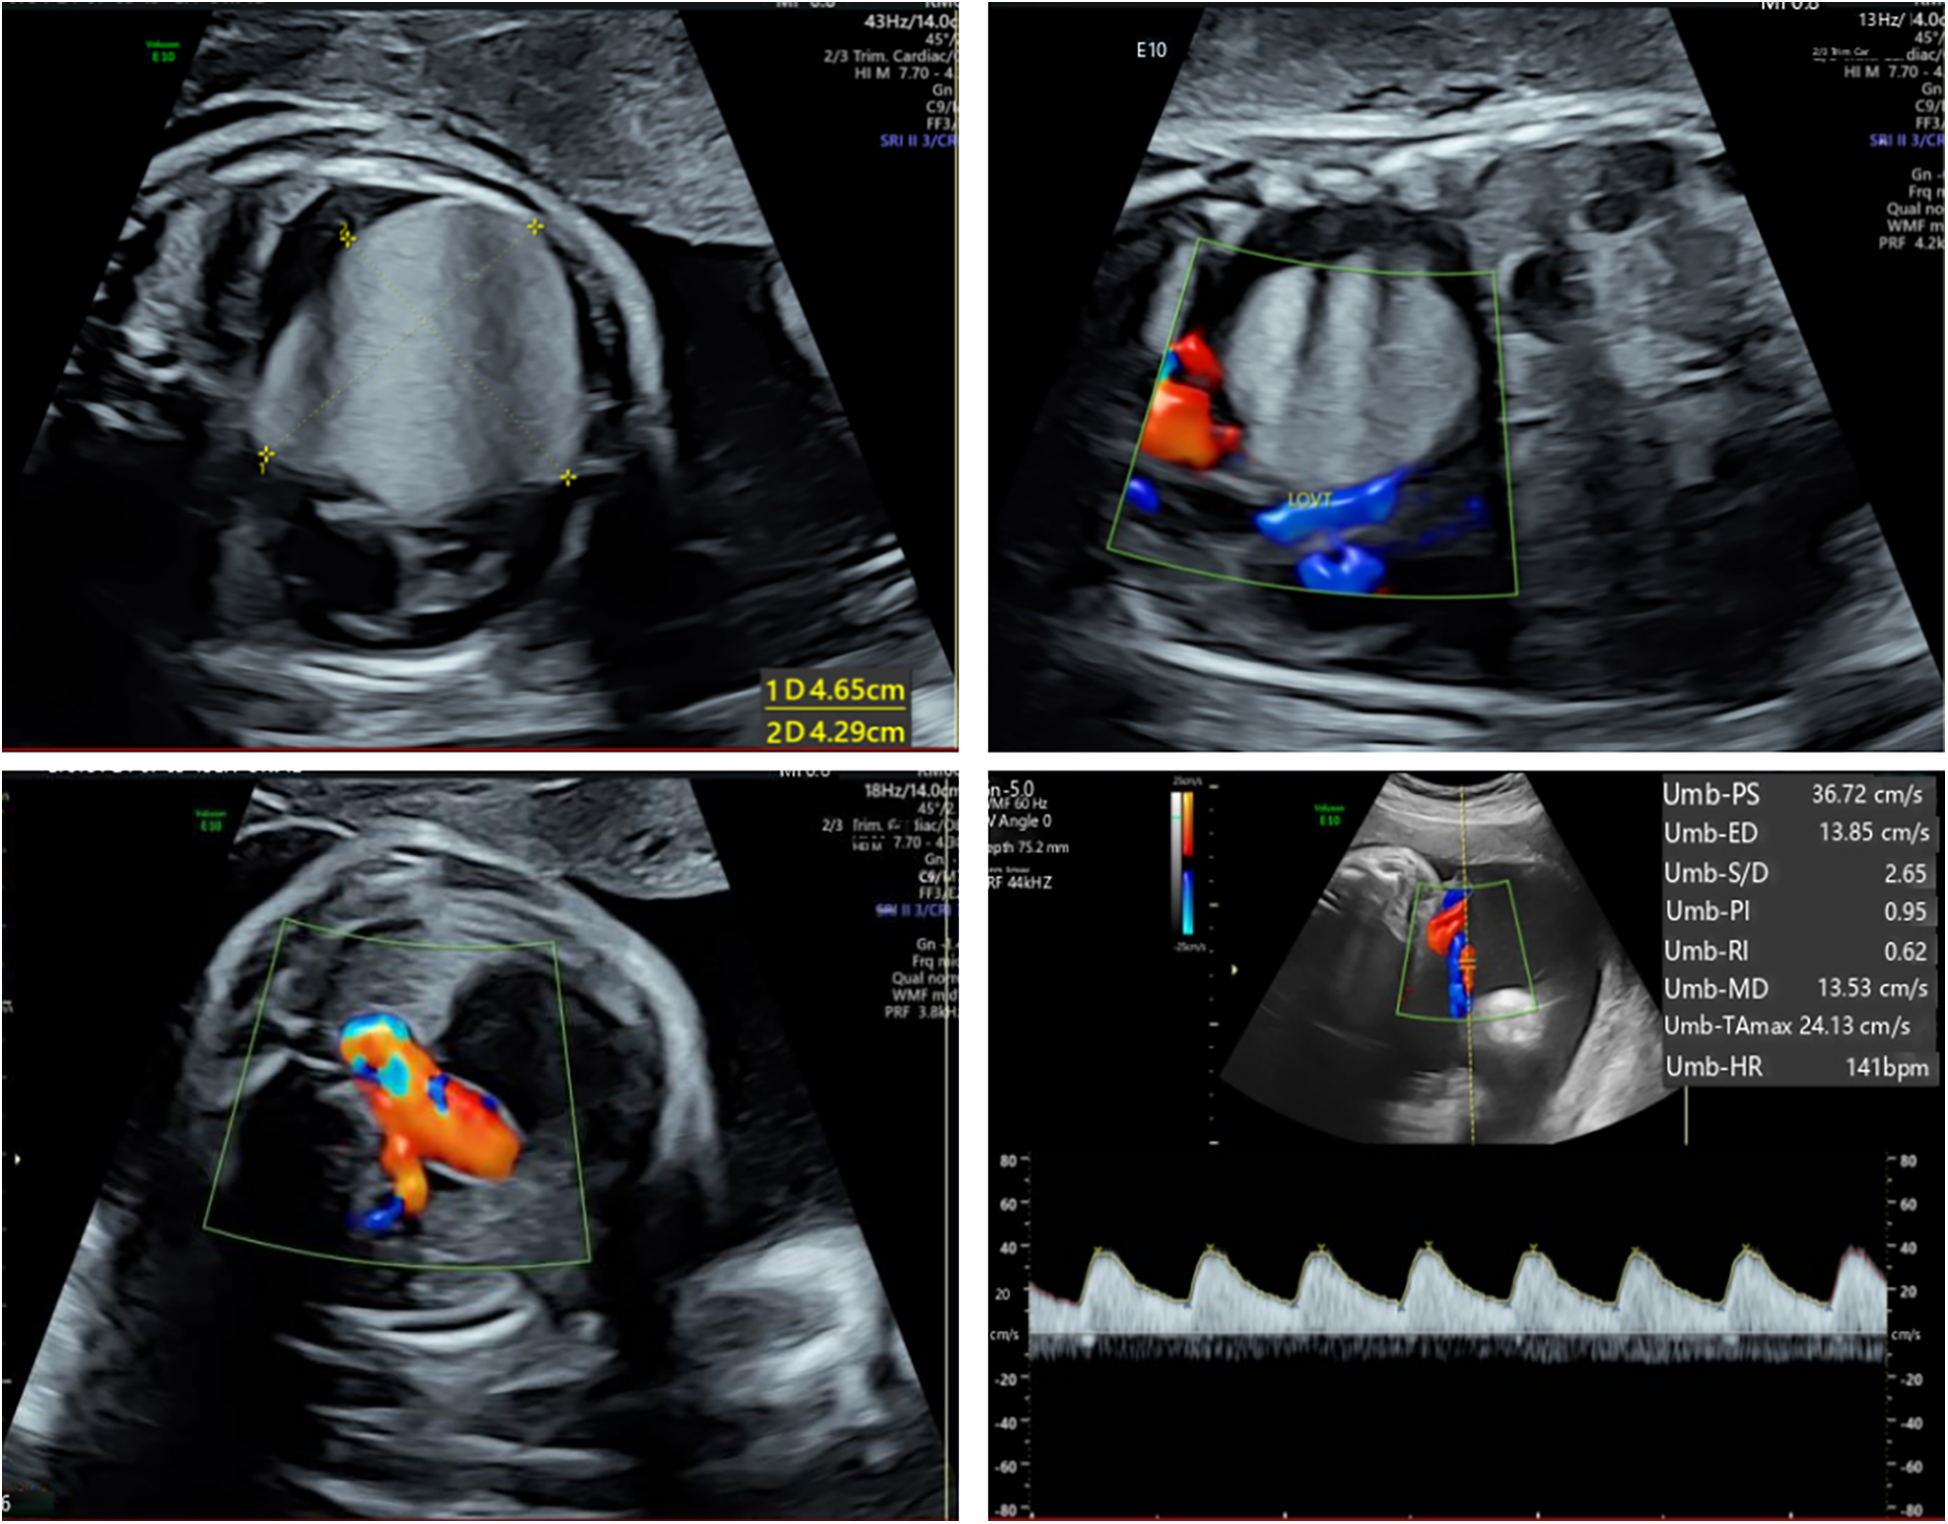

The patient's mother was a 33-year-old Chinese woman who had not been exposed to any toxins, drugs, or other potential teratogenic substances during her pregnancy. Moreover, she had no family history of tumors. At 34 weeks' gestation, fetal echocardiography identified a hyperechoic mass in the left ventricle measuring approximately 47 × 44 × 40 mm (Figure 1). The mass exhibited uniformly distributed internal echogenicity and was well delineated from the surrounding myocardial tissue. Color Doppler ultrasound demonstrated an absence of blood flow within or around the mass. Notably, the mass extended partially into the left ventricular outflow tract, raising concerns about potential obstruction. Additional findings included mild tricuspid regurgitation, a slightly narrowed aortic arch, and a small pericardial effusion. Subsequent amniocentesis for fetal chromosomal karyotyping, chromosomal microarray analysis (CMA), and Trio whole-exome sequencing (Trio-WES) did not reveal any pathogenic variants.

Figure 1

Fetal echocardiography at 34 weeks gestation. Fetal echocardiography detected a hyperechoic mass in the left ventricle, measuring approximately 47 × 44 × 40 mm.